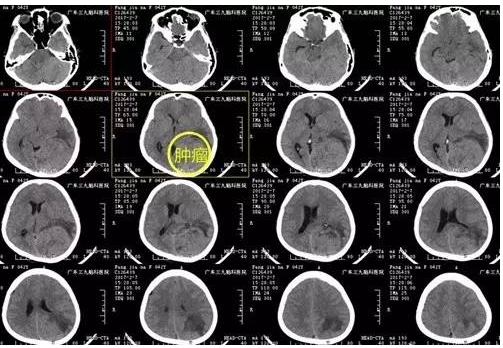

方女士,42岁,半年前开始出现反复头痛、头晕,能自行缓解,近来头痛加重,无法耐受,来医院就诊,门诊CT显示肿瘤呈等密度,瘤周低密度影,遂安排入院治疗。

↑术前CT

大型小脑幕脑膜瘤是指肿瘤基地附着于小脑幕或小脑幕切迹处,瘤径>3cm的脑膜瘤。起源于小脑幕的脑膜瘤仅占颅内脑膜瘤的2%-9%,骑跨小脑幕巨大脑膜瘤则更为少见。由于早期缺乏特征性表现而诊断困难,出现小脑症状及颅高压症状时肿瘤已生长巨大。患者术前为颅内压增高的头晕头痛症状,检查发现时范围已达8.0cm*7.2cm*6.5cm。